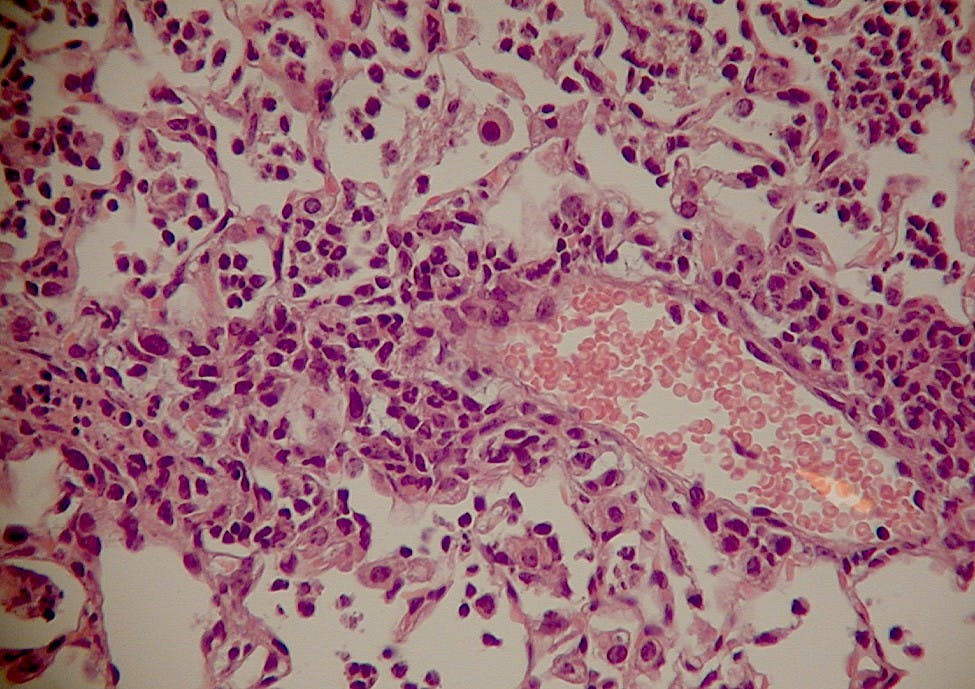

By Xiaoying Li | April 6, 2017Researchers Borna Mehrad and Kathryn Michels have discovered a possible alternative to antibiotics for the treatment of bacterial pneumonia.

Researchers Borna Mehrad and Kathryn Michels have discovered a possible alternative to antibiotics for the treatment of bacterial pneumonia.